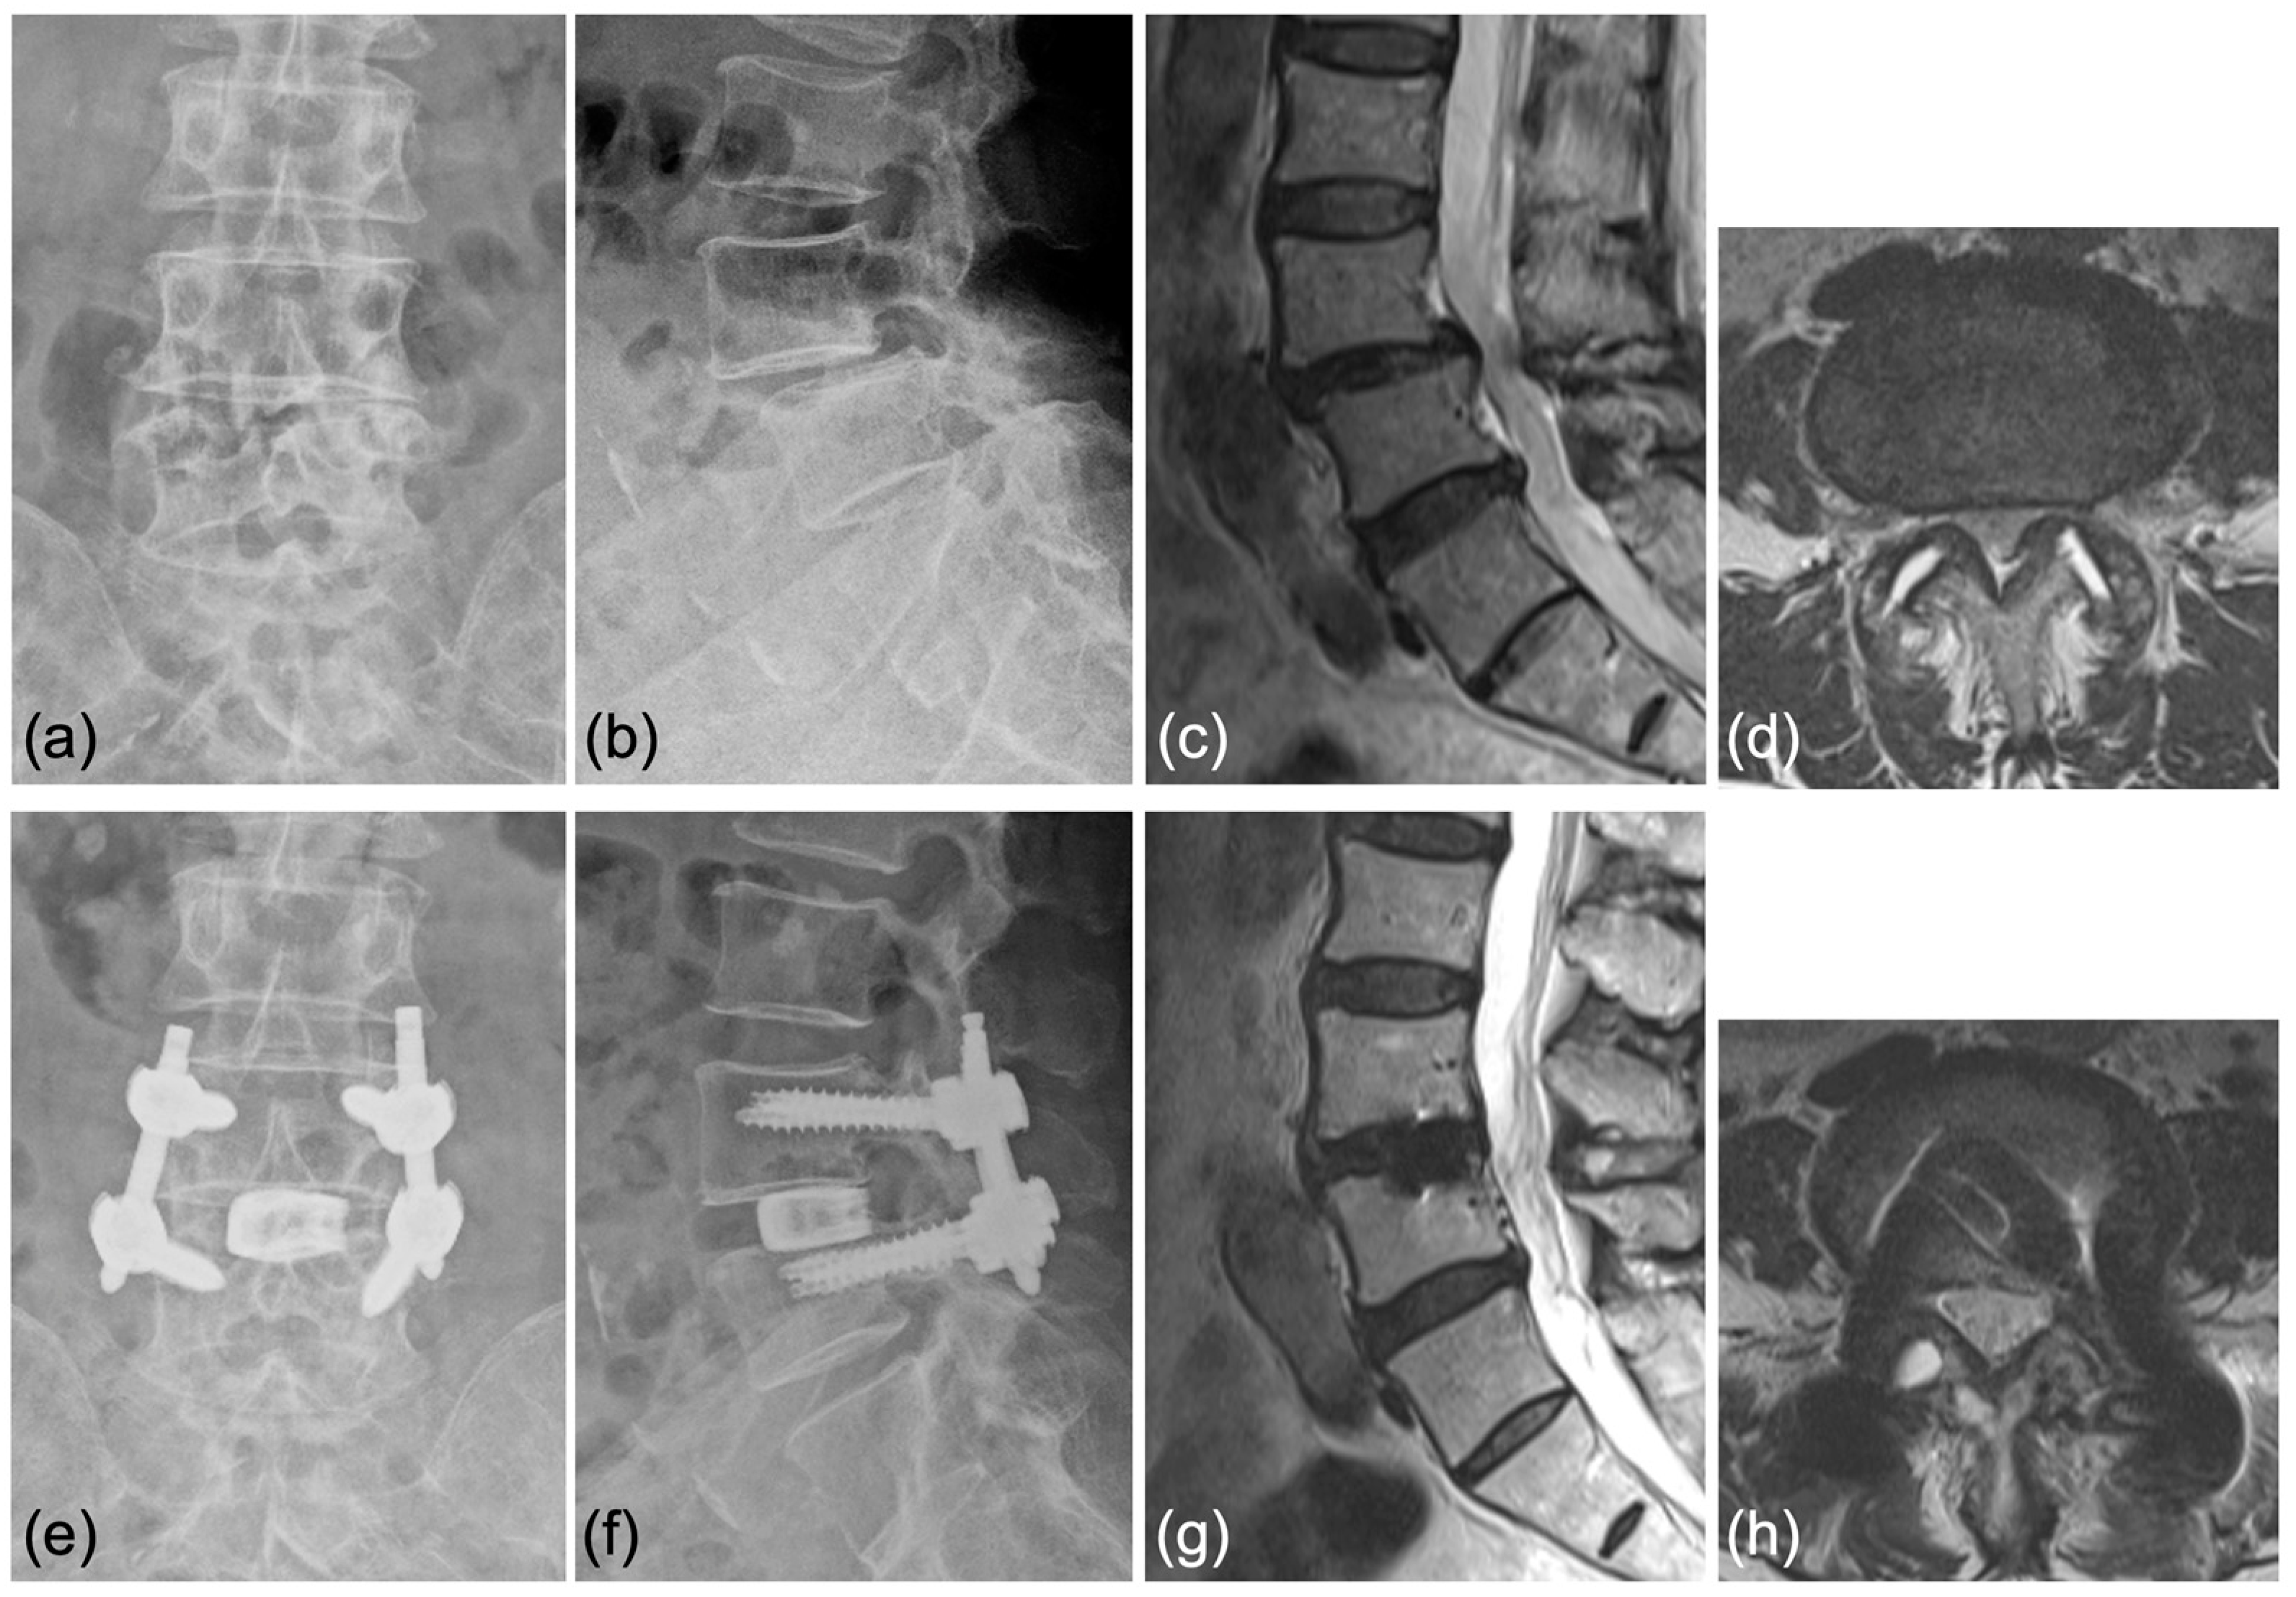

Case 1: A 70-year-old woman was diagnosed with degenerative spondylolisthesis of the L4 vertebra with instability by X-ray, CT, and MRI. VAS for back and leg pain were 100 and 60 mm, and the JOA score was 18/29. The spinal canal area was 95 mm2 at L4/5 disc level, and the % slip was 21% (Figure 7a–d). After the failure of conservative treatment, PETLIF was performed. One month after surgery, VAS back and leg pain improved significantly to 0 and 10 mm. Postoperative X-ray and MRI showed that the % slip was 0%, and the spinal canal area was expanded to 153 mm2 (Figure 7e–h). Bone fusion of L4/5 was confirmed by X-ray and CT scan one year after the surgery (Figure 8a–d).

Figure 7.

(a,b) Preoperative X-ray showing 2° L4 spondylolisthesis. (c,d) Preoperative MRI showed lumbar spinal stenosis at the L4/5 level. (e,f) Postoperative X-ray showed L4 spondylolisthesis was reduced to 0%. (g,h) Postoperative MRI showed the spinal canal area was expanded.

Figure 8.

Bony fusion through the titanium cage was confirmed by (a,b) anterior and posterior flexed lateral X-rays and (c,d) sagittal and coronal CT scans.